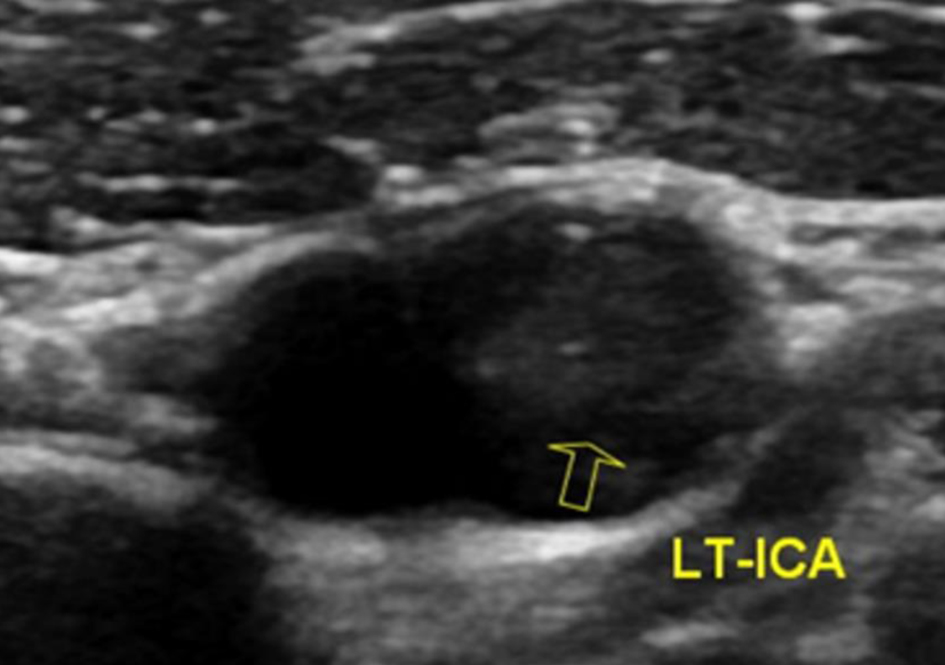

The following day, no apparent hemorrhagic extension was observed. On carotid artery ultrasonography, there was a mobile lesion at the origin of the left ICA (Fig. 2). Further examination with three-dimensional computed tomography angiography (3D-CTA) revealed the presence of irregular contrast in the posterolateral wall of the left cervical ICA origin (Fig. 3a-d). MRI plaque image revealed a structure that was T1 isointense (Fig. 4a) and T2 high intense (Fig. 4b) with the vessel wall, protruding into the lumen (Fig. 4). On the second day, cerebral angiography revealed a shelf-like structure on the posterior wall of the left ICA origin (Fig. 5a), and the left MCA was recanalized. Cerebral angiography revealed pooling of blood flow on the rostral side of the lesion (Fig. 5b).

Figure 2. On carotid artery ultrasonography, there was a mobile lesion at the origin of the left internal carotid artery (yellow arrow).